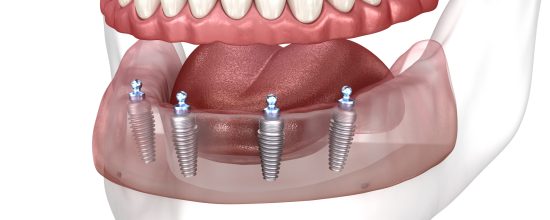

Las prótesis fijas sobre implantes son estructuras dentales que se colocan sobre varios implantes dentales ya integrados en el hueso. Estas prótesis pueden reemplazar múltiples dientes o, incluso, toda una arcada dental.

A diferencia de los implantes individuales, las prótesis fijas sobre implantes son una solución más amplia que permite rehabilitar zonas extensas de la boca. Una de sus ventajas es su capacidad para distribuir la fuerza masticatoria de manera uniforme, proporcionando una funcionalidad similar a la de los dientes naturales. Además, ofrecen una solución altamente estética, ya que se diseñan a medida para adaptarse al color y la forma de los dientes naturales del paciente.